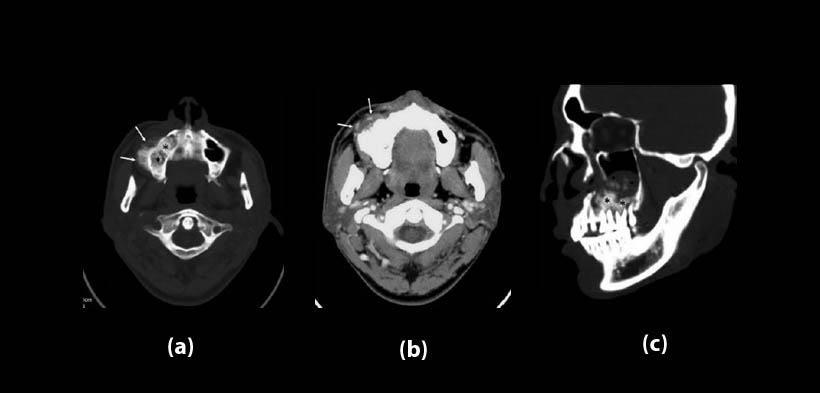

Fig. 1 Osteosarcoma en el maxilar derecho en un hombre de 29 años de edad. (a) TAC, vista axial muestra una gran masa destructiva osteoblástica (asteriscos negro) localizada a nivel del reborde alveolar posterior se extiende hacia el paladar duro y al seno maxilar, se evidencia también la reacción perióstica (flechas blancas). (b) TAC post-contraste, vista axial, se muestra aumento de volumen hacia los tejidos blandos (flechas blancas). (c) TAC, reformación multiplanar sagital, muestra una masa destructiva (asteriscos negros) se extiende hacia el paladar duro y el seno maxilar con calcificación osteoide (puntas de flecha negras)